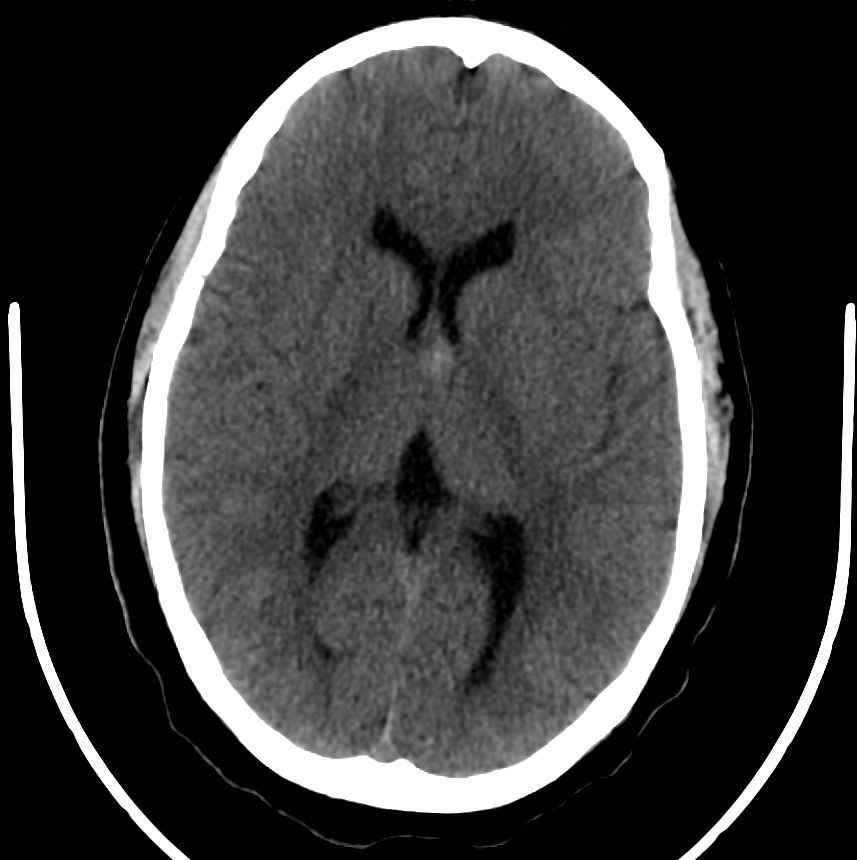

A young female presents with a headache. What do the images reveal?